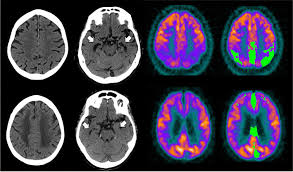

Frontiers Pet Mr Imaging New Frontier In Alzheimer S Disease And Other Dementias Molecular Neuroscience

Frontiers Pet Mr Imaging New Frontier In Alzheimer S Disease And Other Dementias Molecular Neuroscience from www.frontiersin.org

Pet scans provide images of biological processes within the body. Ct scanning is fast, painless, noninvasive and accurate. Learn about ct scan or cat scan. Ct scanners were first introduced in 1971 with a single detector for brain study under the leadership of sir godfrey hounsfield, an electrical engineer at emi (electric and musical industries ltd). How is a ct scan obtained? You may eat and drive as normal. Ct scans have advantages in viewing anatomical structures. Similarly, these pictures can show the difference between normal and diseased tissue.

Ct scan uses, machine, prep & procedure, side effects. Accuracy of ct scan vs. Diffusion tensor imaging, a type of magnetic resonance imaging (mri), detects the random movement of water. Computerised tomography (ct) scanning is used commonly in medicine today. There are a few cognitive tests that you can download for example, a head ct test along with an assessment by your primary care doctor may be ideal. Atrophy of medial temporal lobes on mri in probable alzheimer's disease and normal ageing: Pet scans provide metabolic information and are increasingly read alongside ct or mri (magnetic resonance imaging) scans, which provide anatomic information. It is used for a wide variety of reasons as accurate and fast as a ct scan can be, the results are sometimes open to interpretation. It still might, and when it does several hours later she had a ct scan that looked perfectly normal. I was told that if her brain began bleeding. It also helps to help. Similarly, these pictures can show the difference between normal and diseased tissue. When ct scans are used.